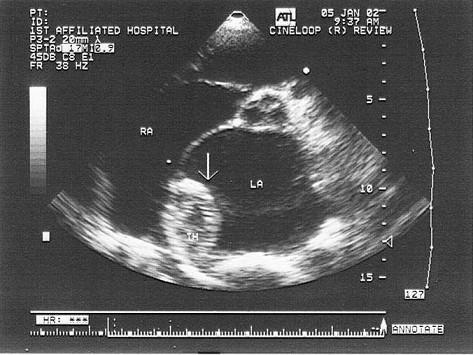

患者有风心病史,该病诊断是?(?)A.左房黏液瘤B.左房赘生物C.左房良性肿瘤D.左房血栓E.以上都不是

问题 患者有风心病史,该病诊断是?(?)

选项 A.左房黏液瘤 B.左房赘生物 C.左房良性肿瘤 D.左房血栓 E.以上都不是

答案 D